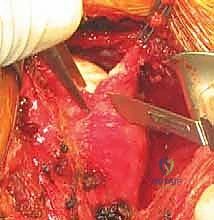

الخطوة 3: زرع الخطاطيف العظمية (Suture Anchors Insertion)

يقوم الجراح بزرع خطاطيف أو مثبتات دقيقة جداً (مصنوعة من مواد تذوب حيوياً أو من التيتانيوم) في حافة العظم الحقاني. هذه الخطاطيف محملة بخيوط جراحية فائقة القوة.

الخطوة 4: إصلاح بانكارت (Bankart Repair)

يتم تمرير الخيوط الجراحية بمهارة عالية عبر الشفا الحقاني الممزق والأربطة المنفصلة. يتم ربط هذه الخيوط بإحكام لشد الأنسجة الممزقة وإعادتها إلى مكانها التشريحي الأصلي على حافة العظم، مما يعيد بناء "المصد" الأمامي الذي يمنع خلع الكتف.